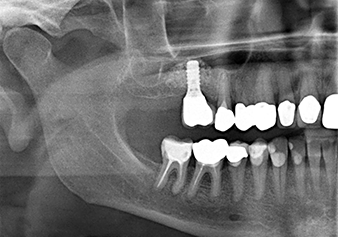

Following an intermediate check (Fig. 4) a further preparation step was performed (Fig. 5). Afterwards, the hydraulic Z35P instrument was used to lift the membrane to the desired position (Fig. 6 and 7). This was followed by further piezosurgical preparation of the implant bed, concluded with a rotary bur and shoulder milling cutter up to the implant diameter of 4.8 mm. Before the implant was inserted, the augmentation material (particle size approx. 0.8-1.6 mm) was introduced underneath the Schneiderian membrane (Fig. 8).

Implantation and prosthetic restoration

To move the augmentation material in the direction of the maxillary sinus atraumatically, the implant was inserted very slowly by hand (Fig. 9). In the process, the membrane was pushed in the cranial direction once again. After two months, the surgical site healed without irritation. Six months later, the x-ray check showed a significant increase in opacity as an indication of ossification (Fig. 10). The prosthetic restoration was carried out with a metal-ceramic crown.